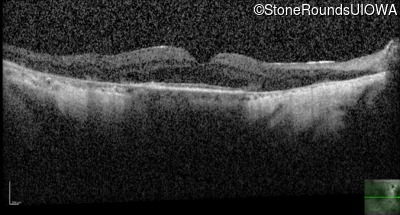

Age at visit: 53 years

This 54 year old man first experienced some reduction in his night vision at age 32. He had been treated with chloroquine for malaria for two years in his early 20s.